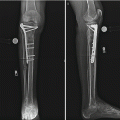

The second mandatory condition of configuration of the device for increasing knee joint ROM is installation of axial hinges strictly according to an axis of rotation of a knee joint (Fig. 11.2).

Fig. 11.2

(a–d) Orientation of the axis of knee flexion–extension in frontal (a), sagittal (b), and transverse (c) planes. Axial hinges are installed between the transosseous modules fixing the femur and the lower leg 2 cm from the joint surface and at the junction of the middle and posterior thirds of the femoral condyle (d)